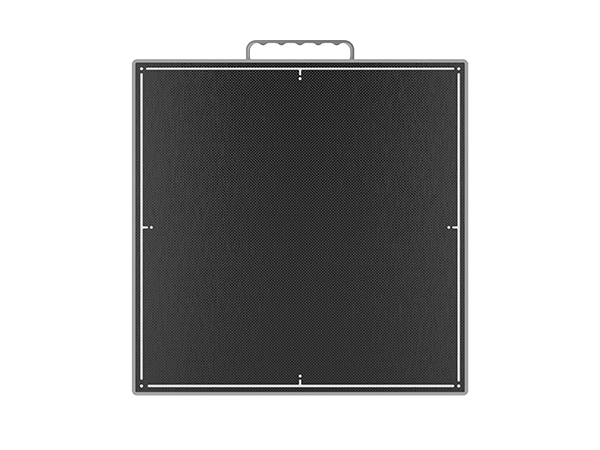

Detector de paneles planos digitales 1417 para radiología de rayos X veterinarios

El detector digital de panel plano 1417 para radiología veterinaria está diseñado para proporcionar imágenes de alta resolución que permiten diagnósticos precisos en una amplia variedad de animales. Su avanzada tecnología DR garantiza una captura rápida y eficiente, reduciendo la exposición a la radiación sin comprometer la calidad de imagen.

Gracias a su diseño ligero y portátil, este detector se integra fácilmente en sistemas de rayos X veterinarios existentes, lo que lo convierte en una opción ideal tanto para clínicas fijas como para servicios móviles. Su versatilidad permite realizar estudios radiológicos en animales pequeños, medianos y grandes, optimizando el flujo de trabajo en entornos de alta demanda.

El panel plano 1417 ofrece una excelente relación señal-ruido y rápida transferencia de imágenes, lo que mejora la eficiencia diagnóstica y reduce los tiempos de espera. Además, su estructura robusta y duradera garantiza un rendimiento confiable incluso en entornos de uso intensivo.

Este detector es una herramienta esencial para clínicas veterinarias modernas que buscan calidad de imagen superior, rapidez operativa y seguridad en los procedimientos, contribuyendo a diagnósticos más precisos y a una mejor atención animal.

Los parámetros específicos

|

ELEMENTOS

|

PARÁMETROS

|

|---|---|

| Tamaño de píxel | 150 µm |

| Tecnología de detectores | Silicio amorfo |

| Centelleador | CsI |

| Área activa (pulgadas) | 14″ × 17″ |

| Dimensión (mm) | 384 × 460 × 15 |

| Conexión | Inalámbrico |

| Tiempo (s) de imagen completa | 5 segundos |

| Conversión AD | 16 bits |

| Tamaño del casete | Y |

| DEA | Opcional |

| Sensor de impacto | Opcional |

| AEC | norte |

| Dinámica | norte |

| Autorización del panel | Opcional |

| Protección de entrada | IPX1 |

| Peso | 3,3 kilogramos |

| Correcciones a bordo | Y |

| Autonomía de la batería | 8,5 horas |

| Intercambio en caliente de la batería | norte |